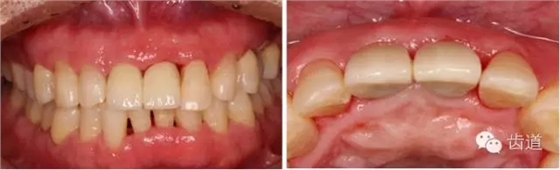

初診照片(正面照)

初診照片(合面照)

治療前后對(duì)比

戴牙一年前后對(duì)比